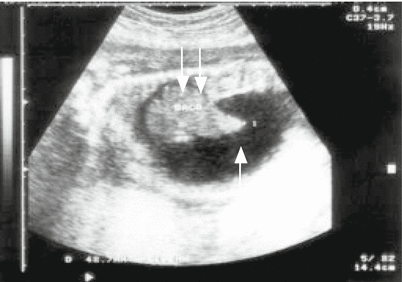

Fig. 15.1

Ultrasound image of a placenta (P) with a thickness of 50 mm (thickened), showing placental involvement in a case of congenital toxoplasmosis